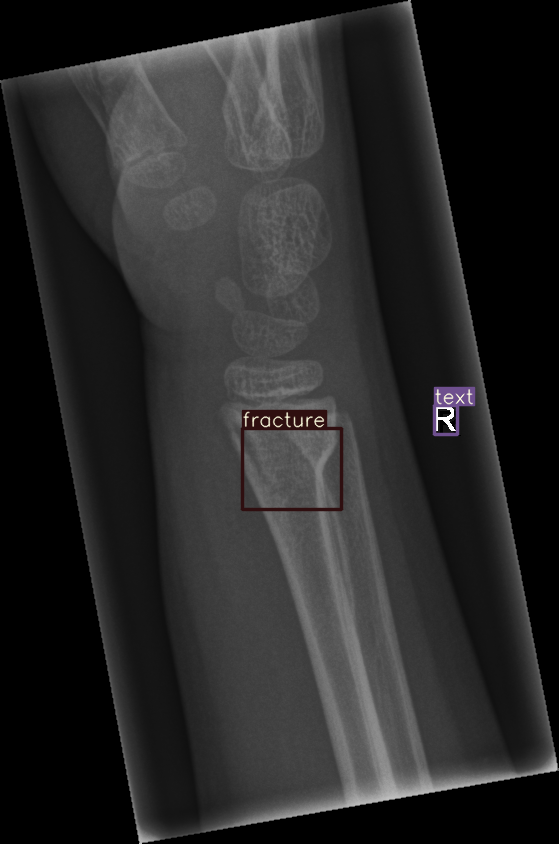

Refer to caption

Figure 4: Bounding box-annotated X-ray images of pediatric wrist trauma from the GRAZPEDWRI-DX dataset [8].

Figure 8: Sample of five images from the GRAZPEDWRI-DX test set, displaying ground-truth and predicted bounding box annotations: (a-e): ground-truth annotations, (f-j): YOLOv11l annotations, and (k-o): G-YOLOv11 annotations.

Table 4: Confidence scores predicted by YOLOv11l and the proposed G-YOLOv11l detectors for five images from the GRAZPEDWRI-DX test set, PR: pronator sign, FP: False positive.

Figure number Class name Confidence score predicted Confidence score predicted

by YOLOv11l by our G-YOLOv11l

8(a) soft tissue, fracture, metal, text -, 0.670.670.670.67, 0.860.860.860.86, 0.830.830.830.83 -, 0.700.700.700.70, 0.890.890.890.89, 0.840.840.840.84

8(b) fracture, text 0.780.780.780.78, 0.710.710.710.71 0.790.790.790.79, 0.730.730.730.73

8(c) fracture, text 0.820.820.820.82, 0.780.780.780.78 0.810.810.810.81, 0.790.790.790.79, (FP: pr 0.44)0.44)0.44 )

8(d) fracture, fracture, text 0.770.770.770.77, 0.700.700.700.70, 0.880.880.880.88 0.760.760.760.76, 0.520.520.520.52, 0.890.890.890.89

8(e) fracture, periosteal reaction, text 0.760.760.760.76, 0.690.690.690.69, 0.760.760.760.76 0.750.750.750.75, 0.600.600.600.60, 0.760.760.760.76

The results in Table 4, derived from Figure 8, compares the confidence scores predicted by YOLOv11l and G-YOLOv11l detectors for five test images from the GRAZPEDWRI-DX dataset. Figure 8 contrasts ground-truth annotations with predictions from YOLOv11l and G-YOLOv11l. G-YOLOv11l shows slight improvements, such as higher confidence scores for "fracture" and "metal" in Figure 8(a) (0.700.700.700.70 and 0.890.890.890.89 vs. 0.670.670.670.67 and 0.860.860.860.86) and for "text" in Figure 8(b) (0.730.730.730.73 vs. 0.710.710.710.71). However, limitations include false positives, such as for "pronator sign" in Figure 8(c) (score 0.440.440.440.44), and lower confidence for some instances, as seen in Figures 8(d) and 8(e). While G-YOLOv11l demonstrates competitive performance, further refinements are required to improve its robustness.